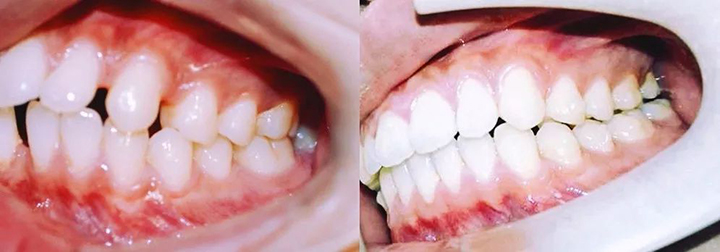

上图就是矫正前后牙齿的对比照,欢迎观看右边照片多一点!

『 排齐上下前牙,关闭前牙散在间隙 』

完整的观察一下目前达到的矫治效果,会发现真的很棒!